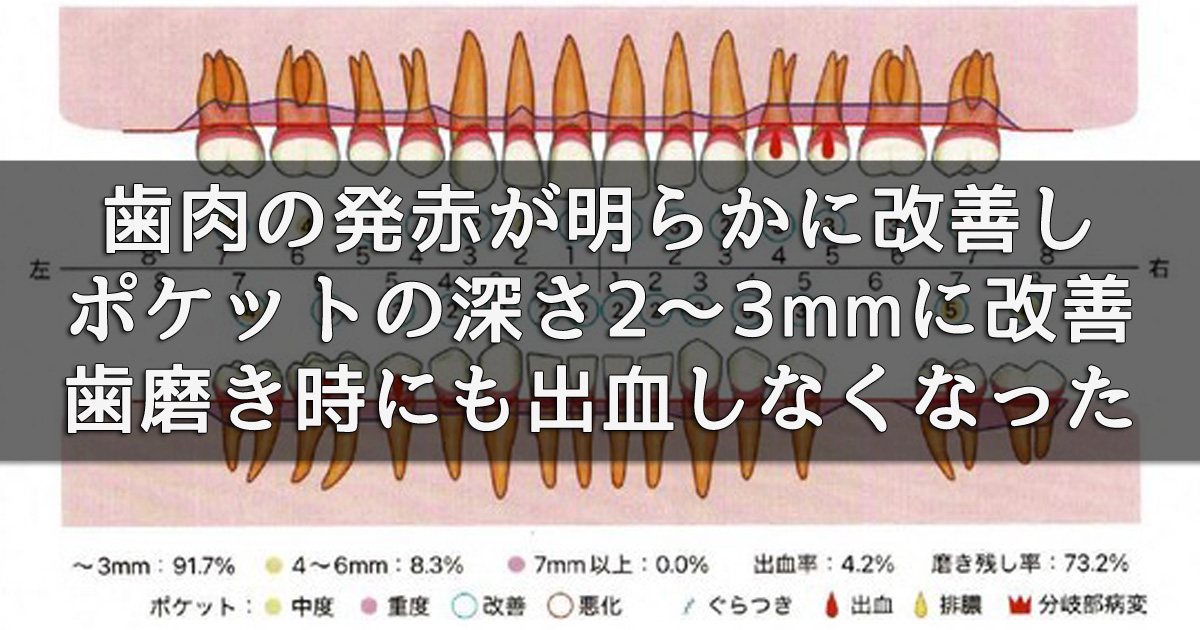

3週間後の再評価では、歯肉の発赤が明らかに改善し、腫れも引いてポケット深さは2~3 mmに改善。歯磨き時にも出血しなくなりました。

3週間後の再評価では、歯肉の発赤が明らかに改善し、腫れも引いてポケット深さは2~3 mmに改善。歯磨き時にも出血しなくなりました。